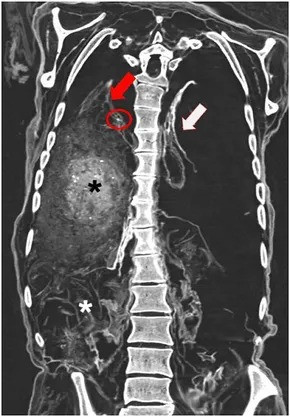

Kết quả kiểm tra cho thấy cha xứ Rosenegg có dấu vết của việc hút tẩu thuốc trong thời gian dài. Nhóm nghiên cứu cũng phát hiện người này có tình trạng vôi hóa và u nang trong phổi. Đây là những đặc điểm phổ biến ở những người mắc bệnh lao mãn tính. Ảnh: J. Wimmer.

Những vấn đề về sức khỏe trên có thể dẫn tới xuất huyết phổi cấp tính. Nhóm nghiên cứu cho hay đây có thể là nguyên nhân tử vong của cha xứ Rosenegg do không tìm thấy bằng chứng nào về ngộ độc. Ảnh: S. Panzer.